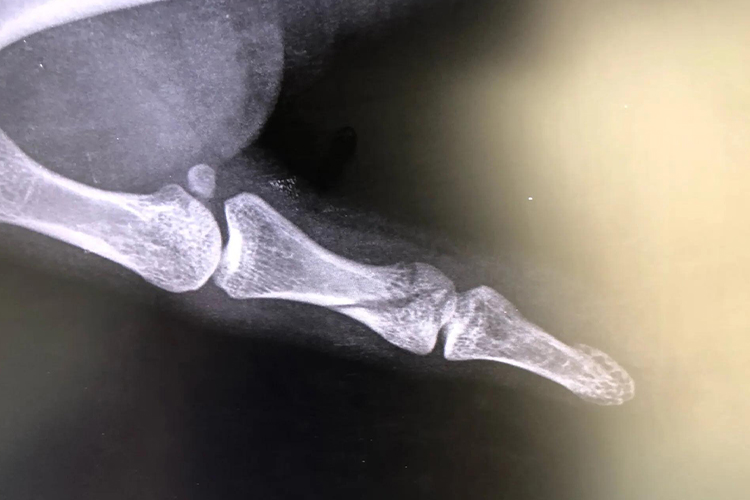

大拇指轻微骨裂时X线显示骨中仍然有一部分的骨组织保持连续性,患者的大拇指会出现局限性压痛,由于软组织损伤可能还会在骨折处周围出现肿胀,外伤后由于血红蛋白的分解,还会出现紫色、青色、黄色的皮下淤斑。